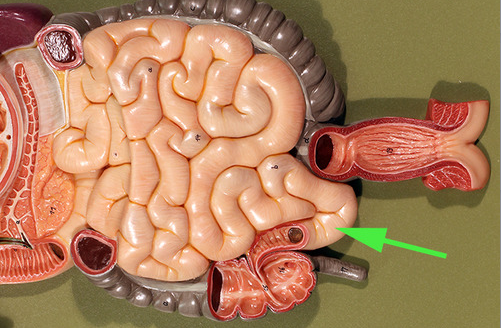

Areas of diffuse lymphatic tissue are found in the walls of the structures marked by the green arrows. They are called the///small intestine

The diffuse lymphatic tissue found in the structure marked by the green arrow is called peyer's PATCH

The green arrow is indicating the peyer's patch in this area of the small intestine. It is made up of a dense accumulation of what kind of cells?//lymphocytes